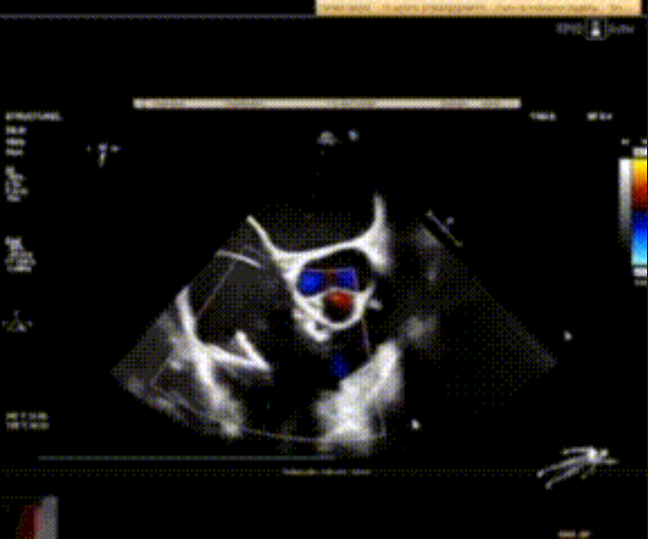

術前心臟超聲提示:極重度三尖瓣返流,右房容積明顯增大,三尖瓣瓣環(huán)顯著擴張。

術后心臟超聲提示:LuX-Valve Plus植入后,三尖瓣瓣環(huán)處可見人工瓣膜回聲,未見返流,人工瓣膜穩(wěn)定,瓣葉開閉良好,連續(xù)多普勒估測三尖瓣平均跨瓣壓差僅為1mmHg。